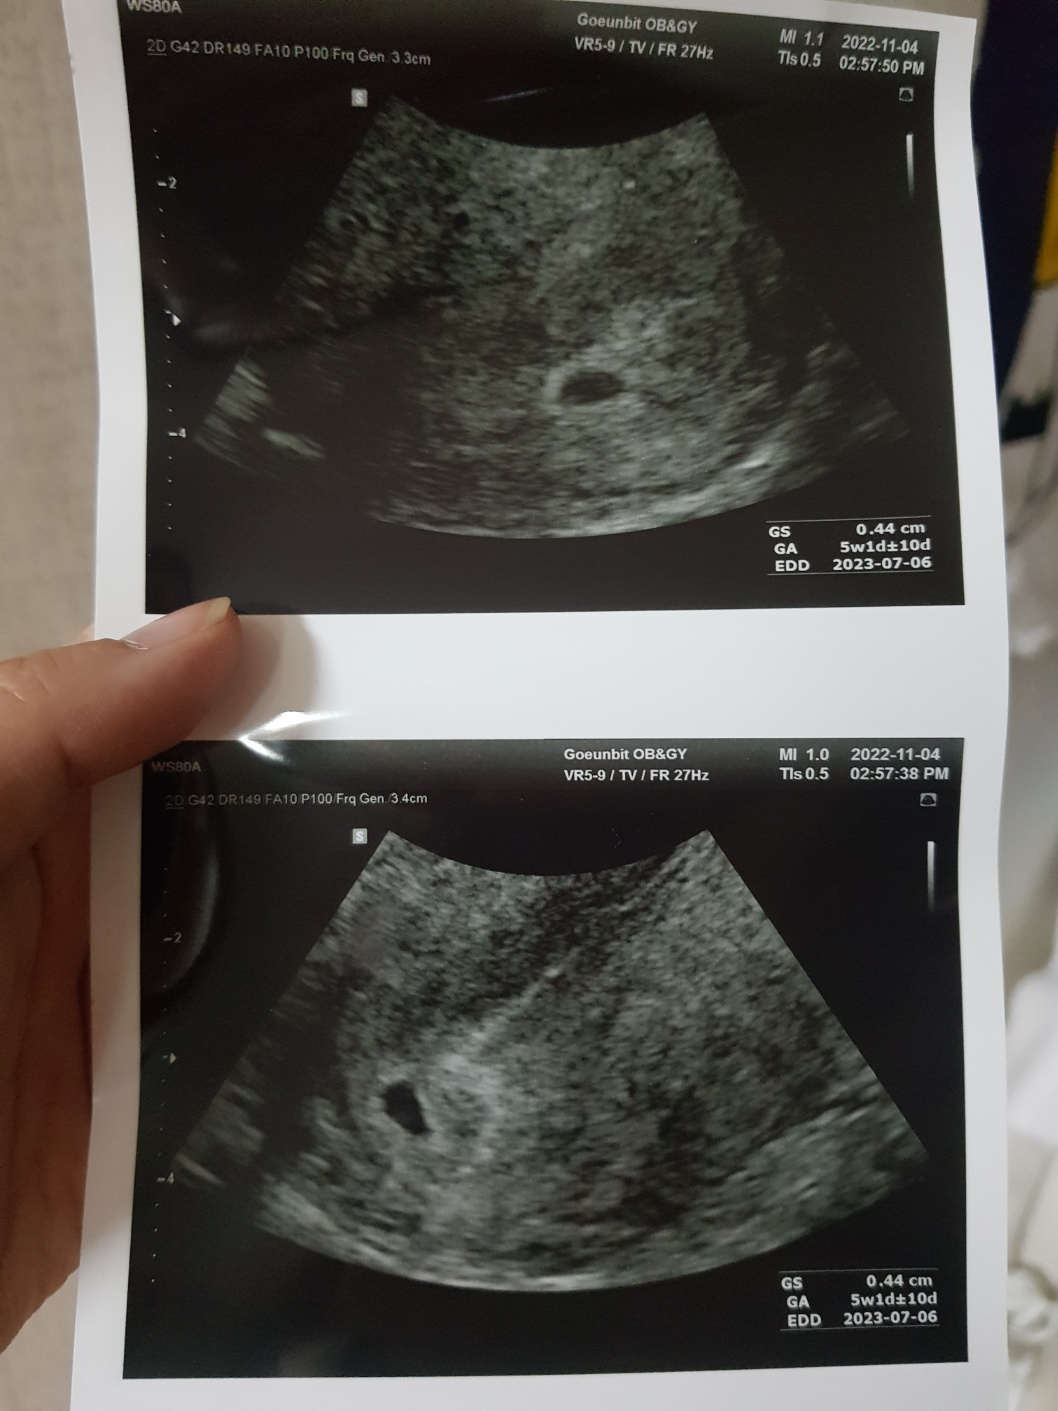

집, 회사에서 가까운 잠실역 근처에 있는

'송파 고은빛 산부인과'에 방문해서 임신여부 확인을 했어요!.

병원 임신여부 확인 결과,

5주 차인 아기집을 확인했고, 임신판정되었습니다!